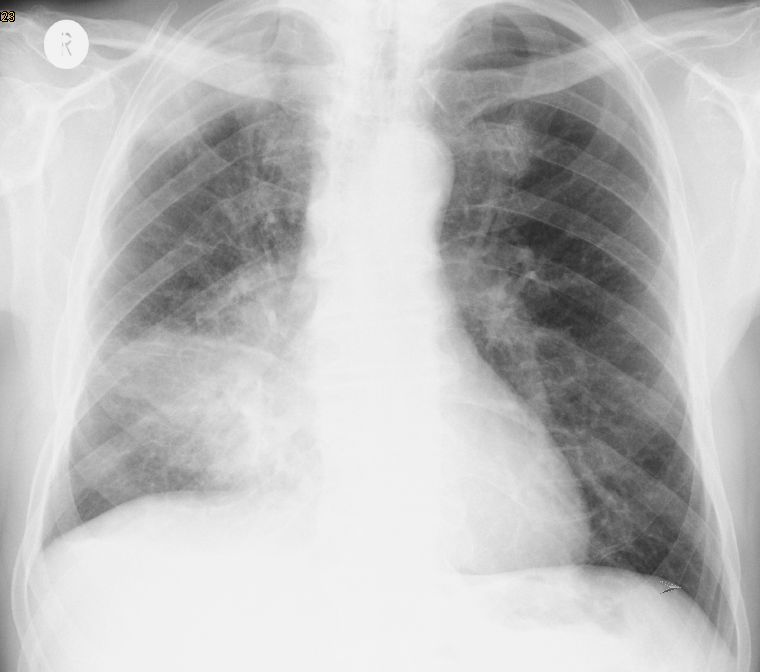

Röntgen Thorax

Kleinzelliges Bronchialkarzinom des rechten Hauptbronchus T4 N2 M1bra.

Kleinzelliges Bronchialkarzinom des rechten Unterlappen T2 N2 M0.

53-jährige Frau mit Dyspnoe und Zeichen der oberen Einflusstauung. Kleinzelliges Bronchialkarzinom rechts zentral.